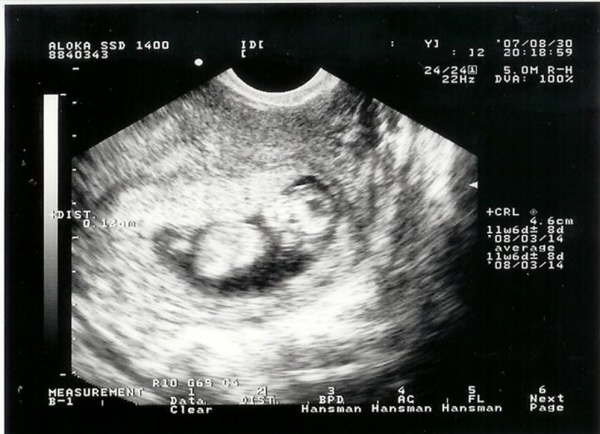

Annyira irígyellek, hogy már ilyen szép fotód van a picurkáról! Én jövőhét csütörtökön megyek uh-ra, de komolyan mondom, sosem fog eljönni az az idő!

Még szívhangot sem láttam/hallottam eddig és már nagyon-nagyon aggódom, hogy rendben van-e minden a Kistesóval!